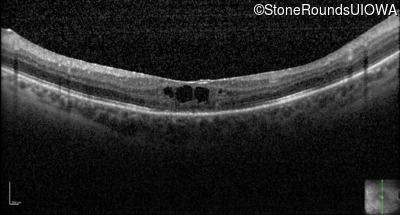

Optical Coherence Tomography - Right - 20/50 +2

Exemplar / OCT Stack

Optical Coherence Tomography - Left - 20/160